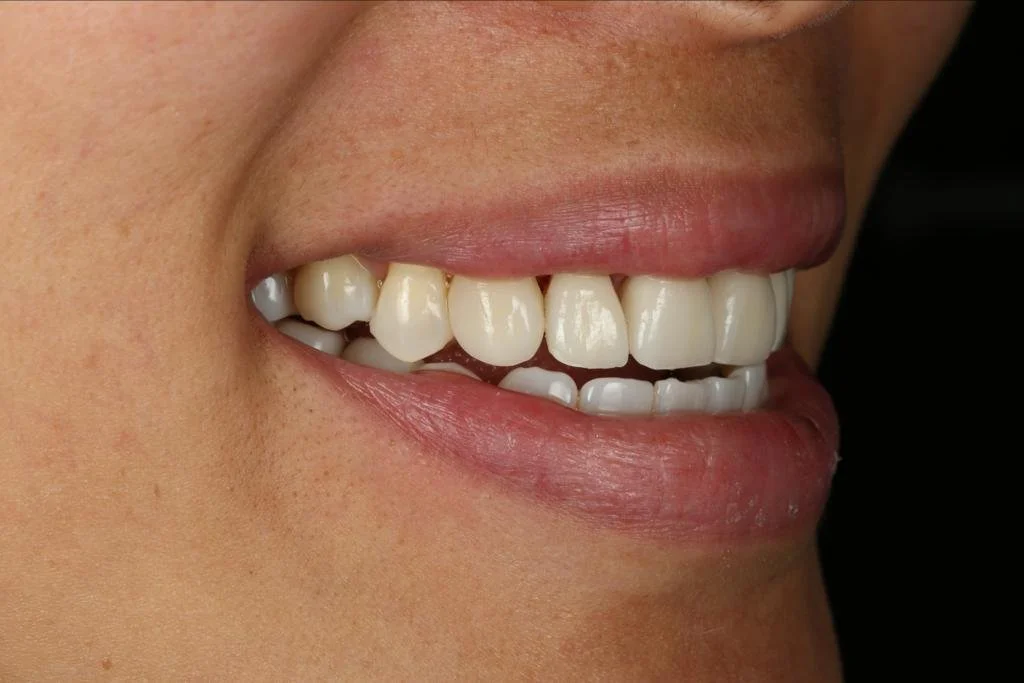

Cerec Reshape and Stain Graze